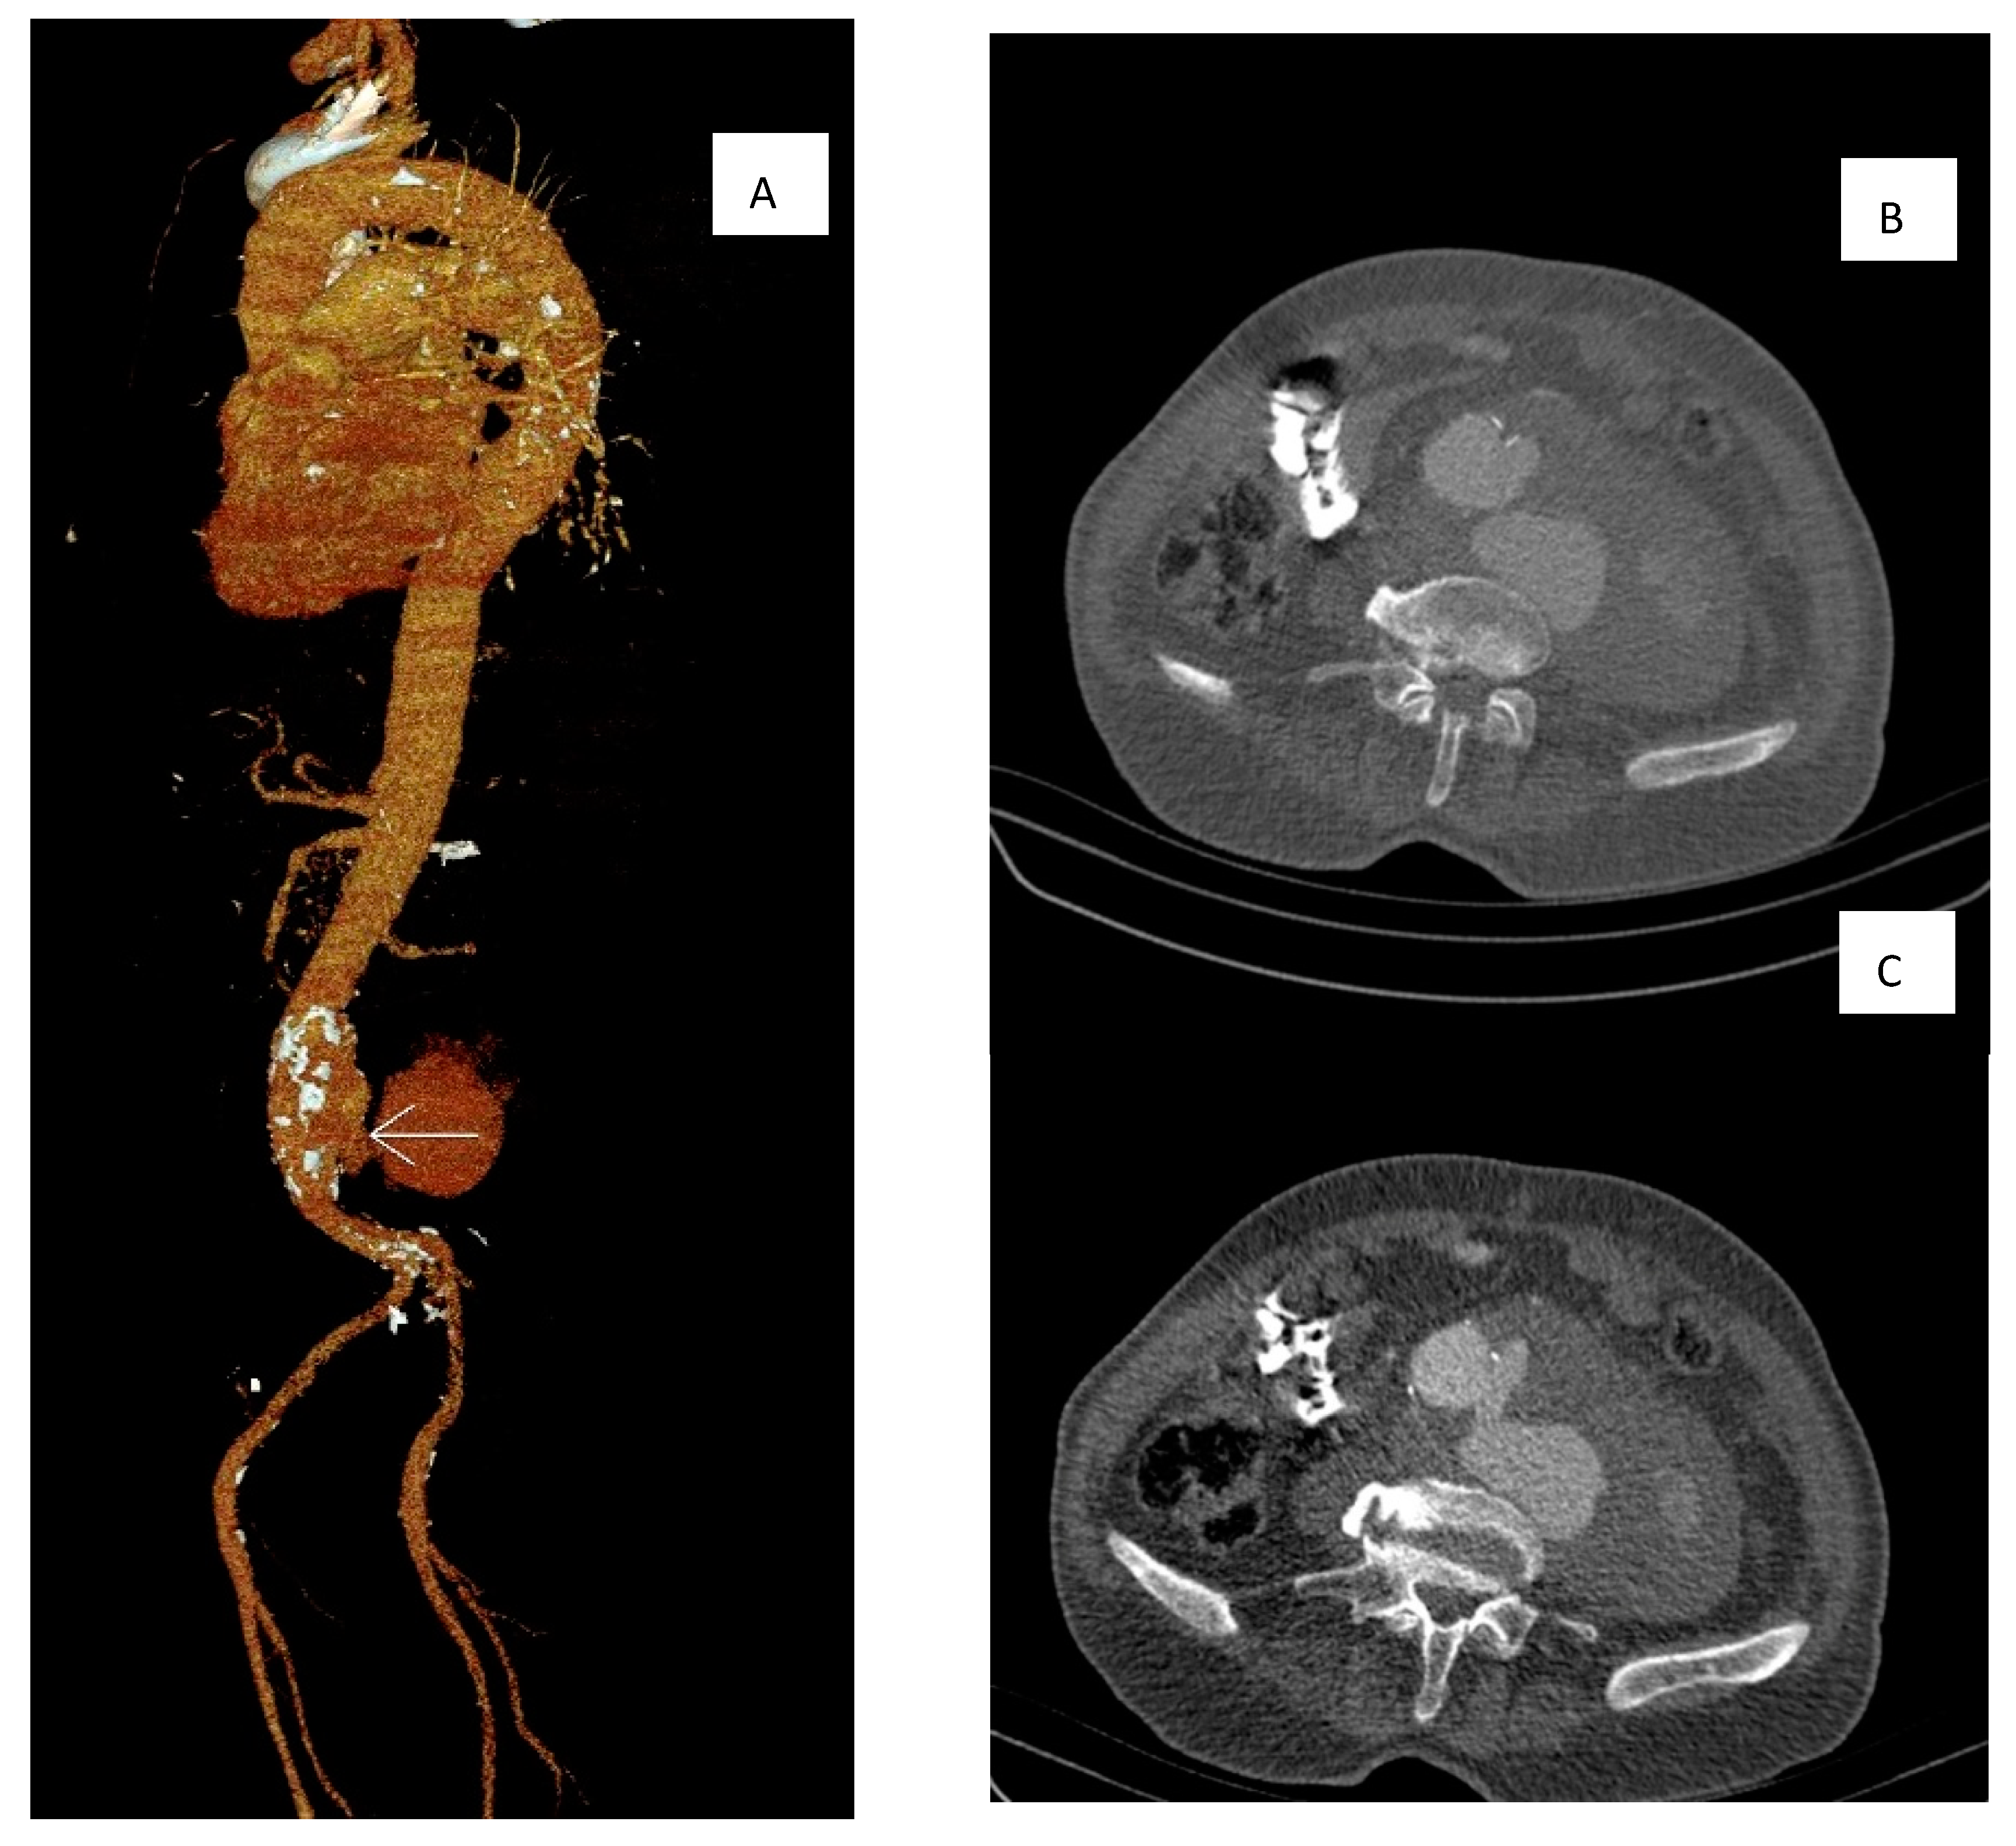

2. Case Description